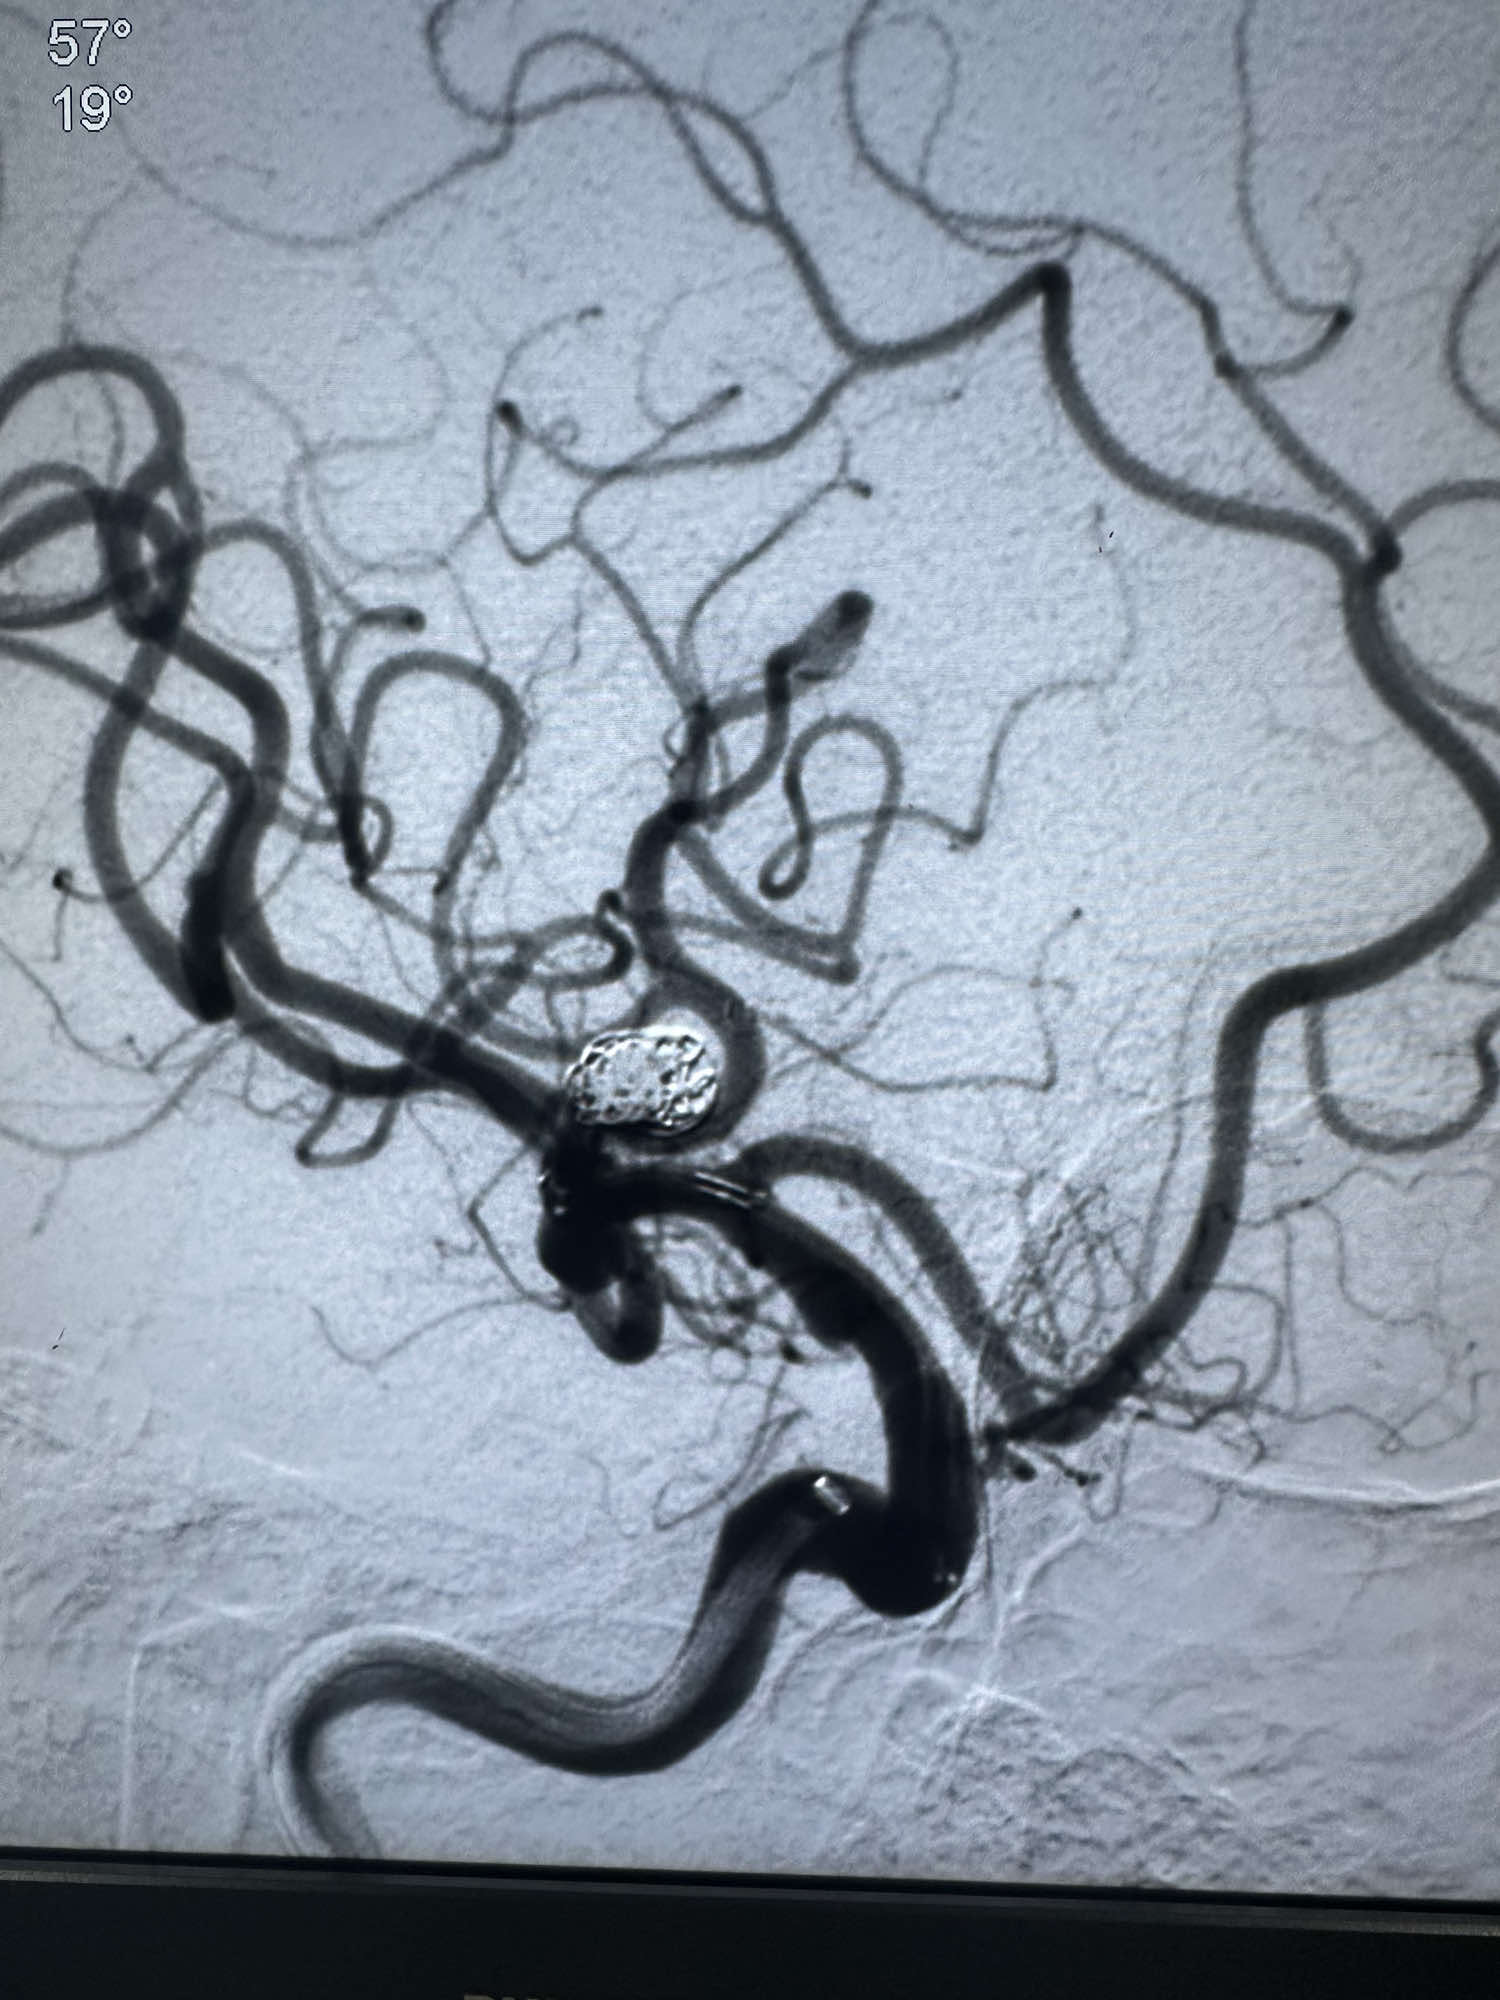

第一枚圈选择6的3D成篮圈,释放支架Atlas 3*15的支架,支架的远端放置在上干

第一枚圈的形态